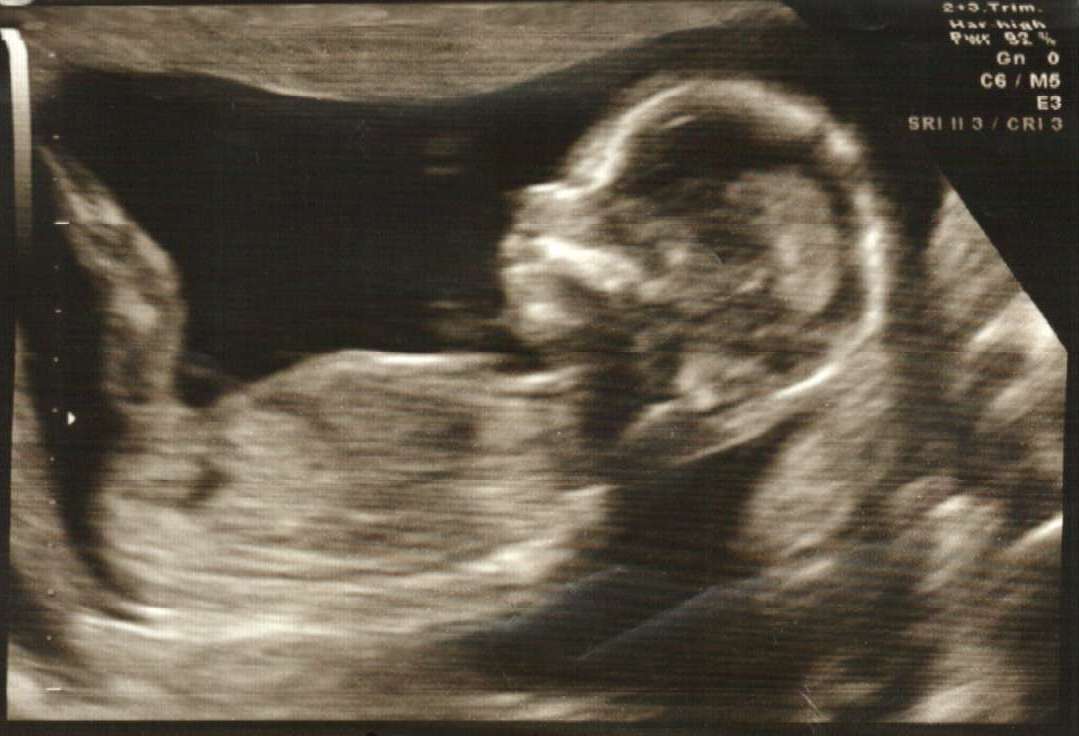

Pls help..........Is it Boy or Girl (clear nub shot) ? Ultrasound (15w4d)

Hi All, Please help us to predict our baby's gender. We had attached ultrasound at the age of 15w4d. But, our OB was not sure to tell the gender of baby. As per her this is too early to tell. The baby's weight is 118g and heart beat is 156. (The picture taken between the two legs of baby) Please tell us.

Do you see any clue in pic 2 and 3 ?